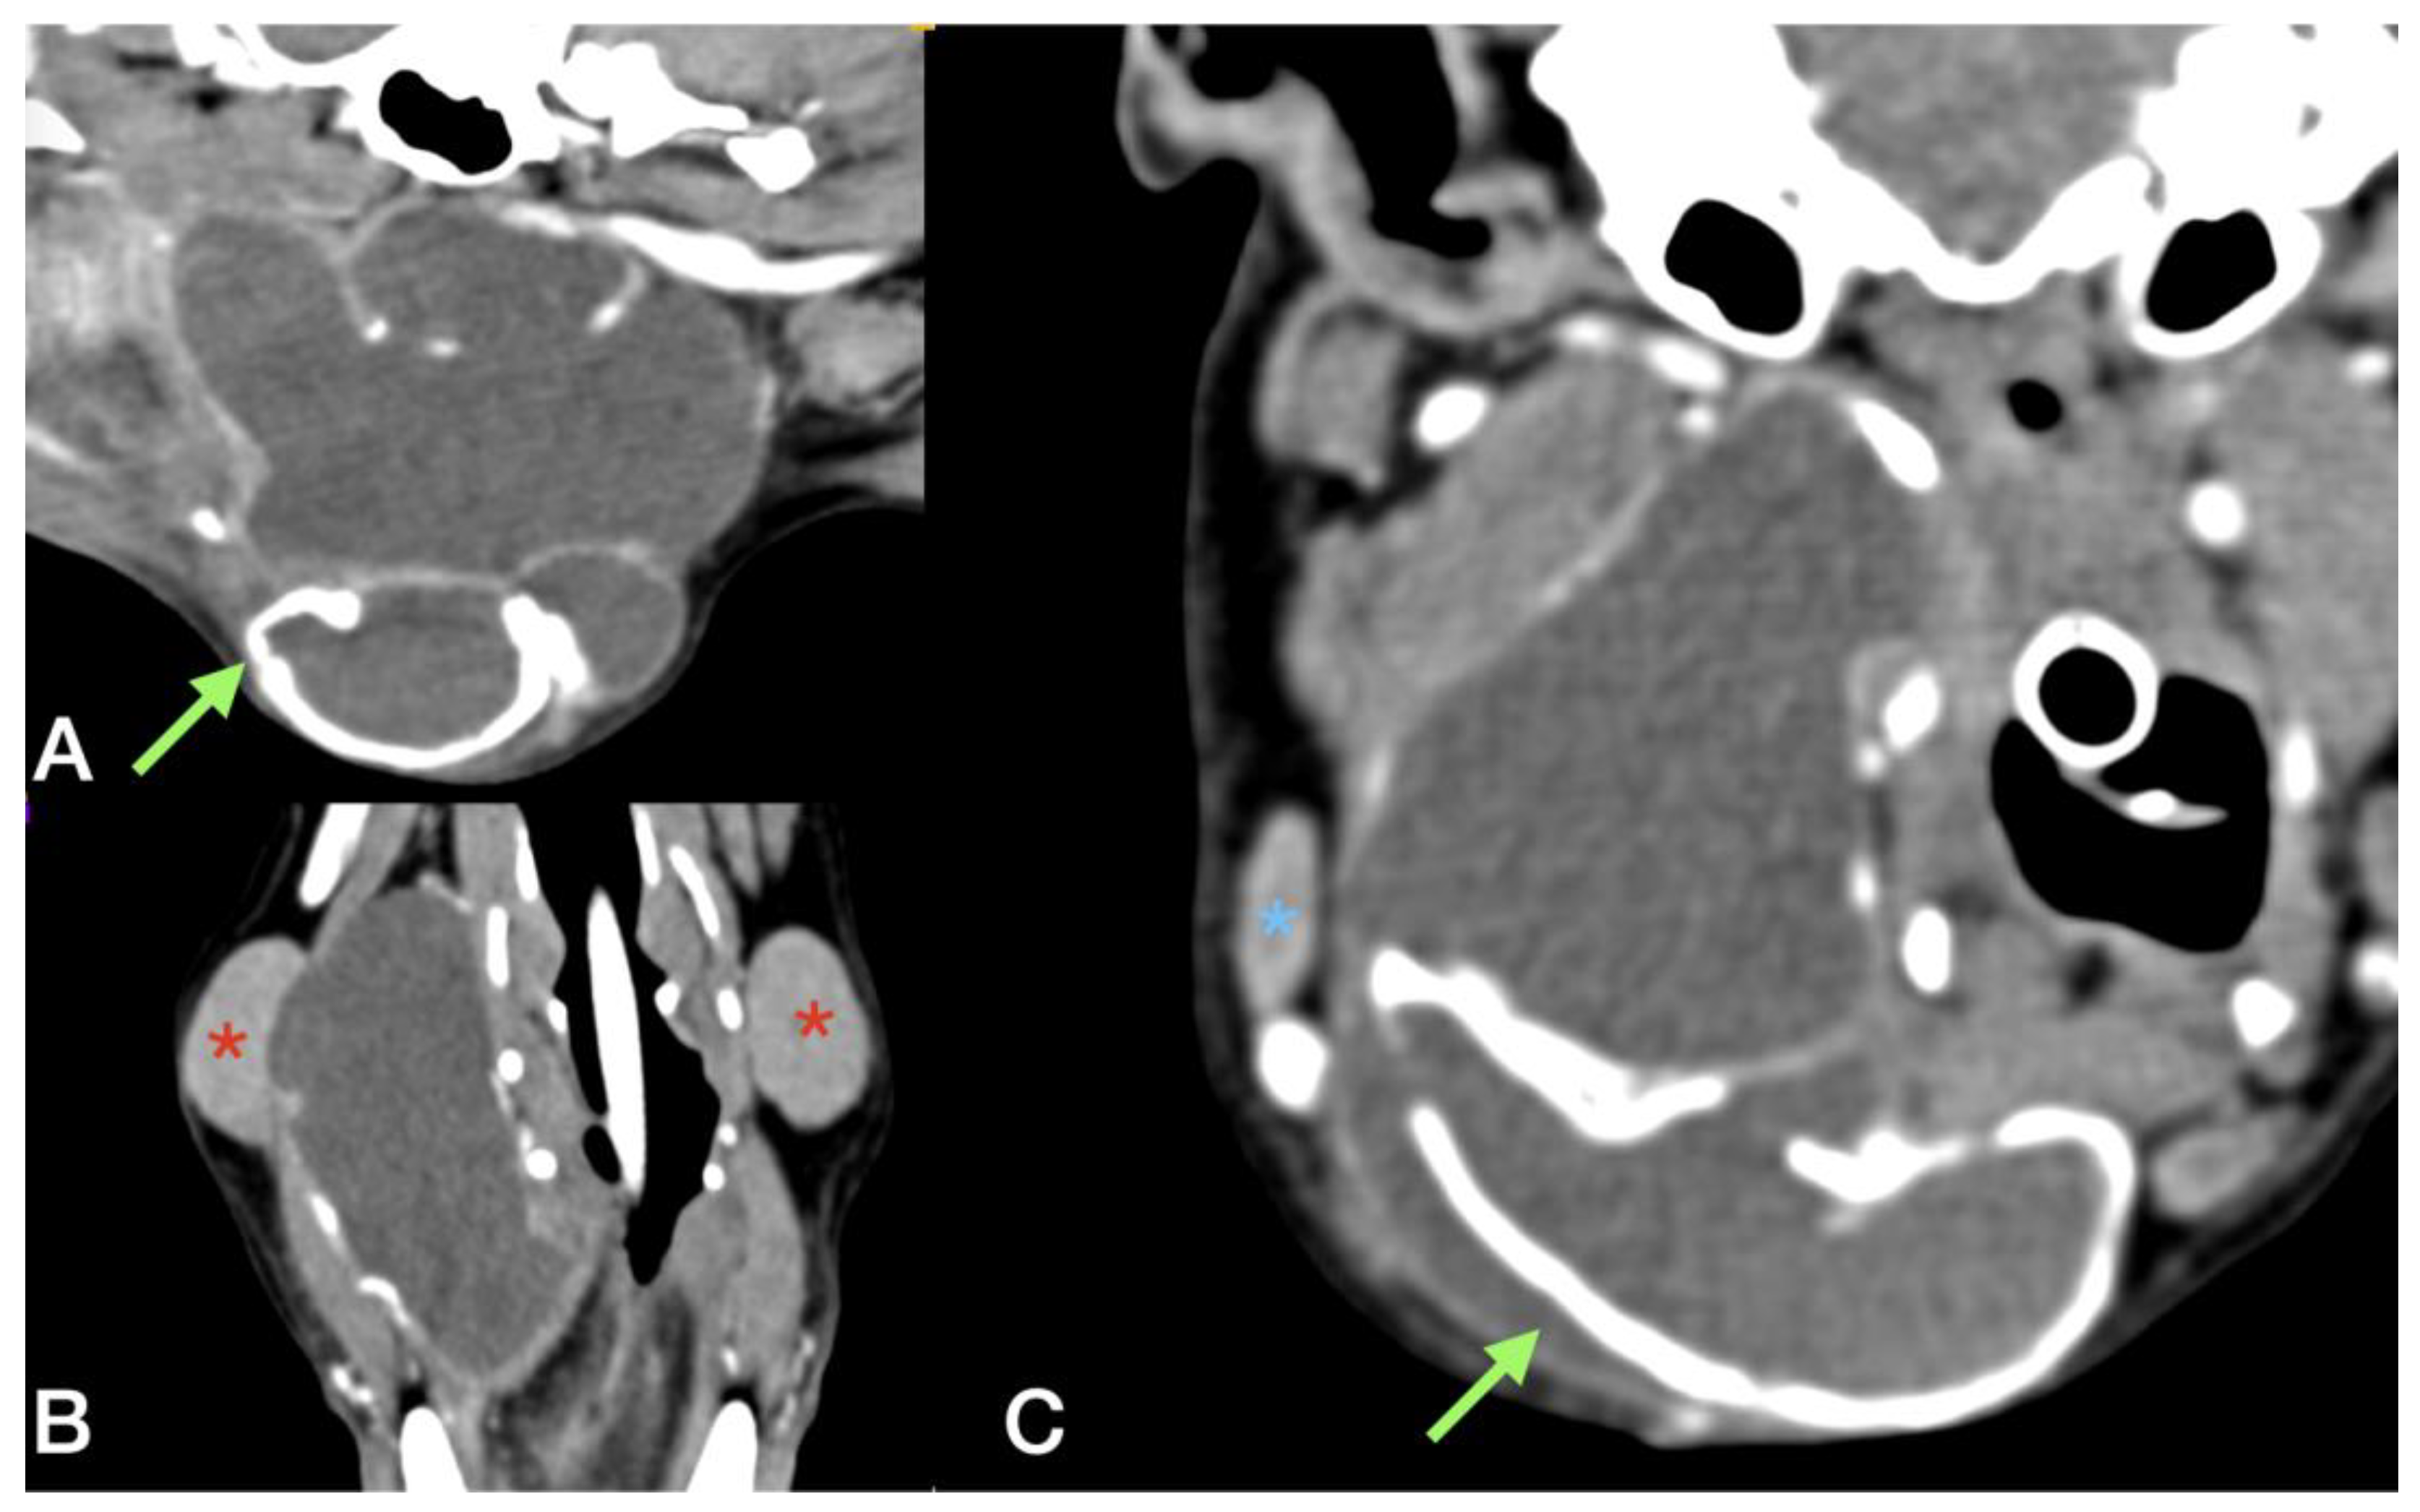

A CT scan revealed a complex cystic formation extending from the right mandibular region, between the tongue and the mandible, up to the ipsilateral laryngeal region. The swelling had dimensions of 4.5 cm (width) × 5.8 cm (height) × 6.1 cm (length) with multiple concamerations and partially mineralised walls (approximately 2 mm thick); the content was fluid attenuating with no contrast enhancement (average attenuation of 20 HU). The medial aspect of the lesion was in contact with the hyoid apparatus and the larynx, which were dislocated and compressed to the left, while the caudal margin was in contact with the right mandibular lymph node and the facial vein. The swelling extended dorsally in the pharyngeal region, reaching the right tympanic bulla and the external carotid artery. The right mandibular SG appeared adherent to the lateral wall of the swelling, resulting in its appearing dislocated and compressed laterally. The right retropharyngeal lymph node was enlarged (2.2 × 1.9 cm) with dishomogeneous contrast enhancement and was in contact with the caudal aspect of the swelling (Figure 6).

Figure 6. Multiplanar reconstruction of post contrast CT scan in dog #3. (A,C) Sagittal and transverse reconstruction: the green arrow underlines the thick and mineralized wall of the sialocele, while the blue asterisk indicates the right mandibular lymph node. (B) Dorsal reconstruction: the red asterisk indicates the mandibular salivary gland. The right salivary gland appears in continuity with the sialocele.